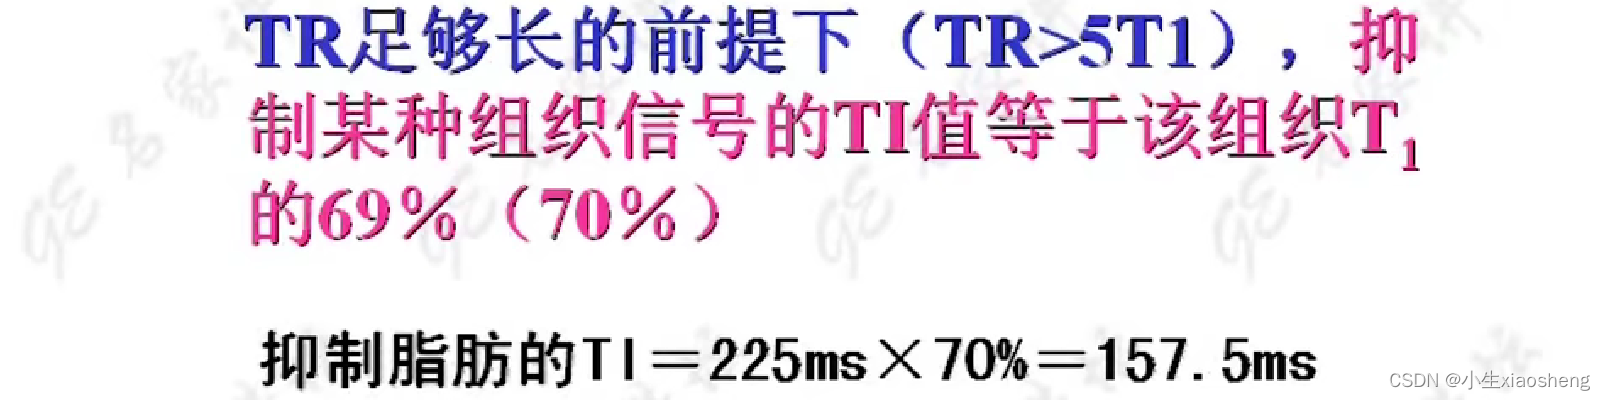

说明时间越长对应的差距也就越大,说明其结果对比好,更容易看出图片。其中TI为反转时间

通过抑制那么在检查的时候就能针对性检查某种组织信号。几种应用我也不想看了😵